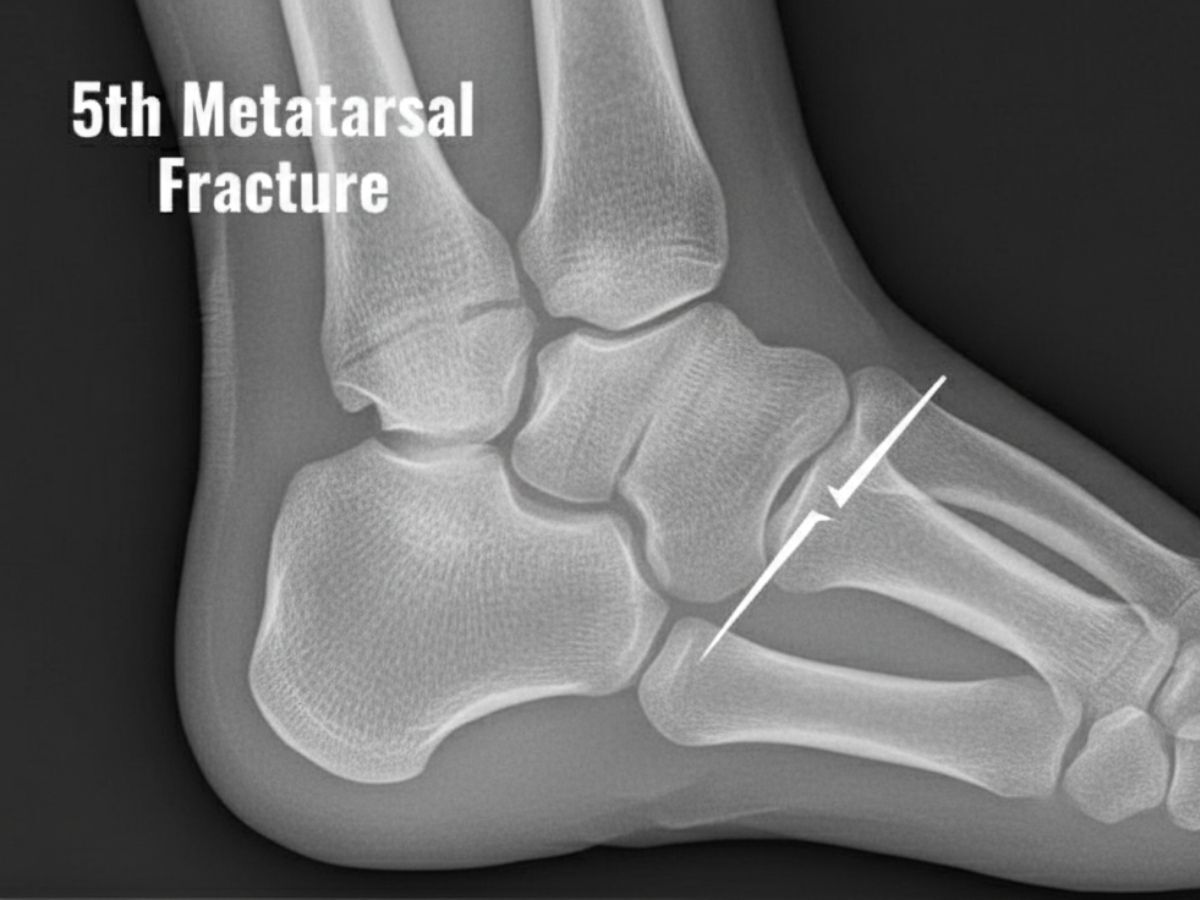

A 5th metatarsal fracture, usually called a Jones fracture, occurs at the base of the fifth metatarsal bone, which is placed on the outer facet of the foot. These fractures can be tough to heal due to the confined blood supply to this area. Consequently, proper treatment is essential to avoid complications and ensure a speedy recovery.

Overview of 5th Metatarsal Fracture